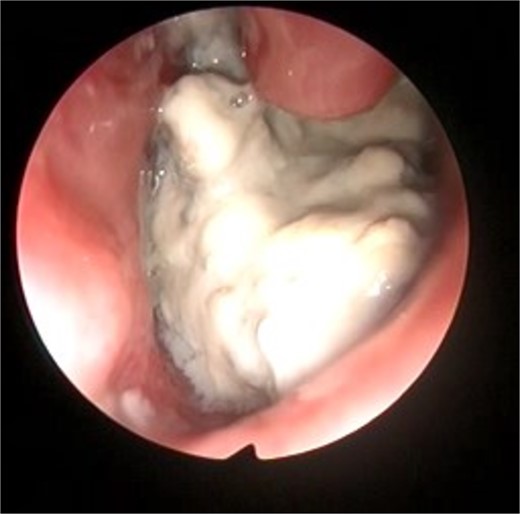

This presentation was clinically suggestive of left-sided rhinolith. Hence, a CT scan was obtained, which showed a well-defined expansile heterogeneous calcified/ossified lesion occupying the inferior aspect of the left nasal cavity measuring 2.5 × 3 × 2.1 cm (craniocaudal × anteroposterior × transverse). Also, the lesion was expanding the nasal cavities with bone remodeling of the medial wall of the maxillary sinus with remodeling and superior displacement of the left inferior turbinate (Fig. 1). These findings were highly suggestive of rhinolith; therefore, the patient was scheduled for a left endoscopic rhinolith removal. Intraoperatively, a giant, calcified nasal lesion was noticed and removed from the left nasal cavity, which was attached to the inferior and middle turbinates (Fig. 2). Furthermore, a biopsy from the lesion was taken for histopathological analysis, showing calcification with fibrin and hemorrhage. These findings confirmed the diagnosis of left nasal rhinolith, and the patient was discharged with no complications. Six months after the procedure, A the patient presented to the clinic with no signs of recurrence, and her endoscopic examination revealed clear nasal cavities (Fig. 3).

Postoperative nasal endoscopic view showing a clear left nasal cavity.